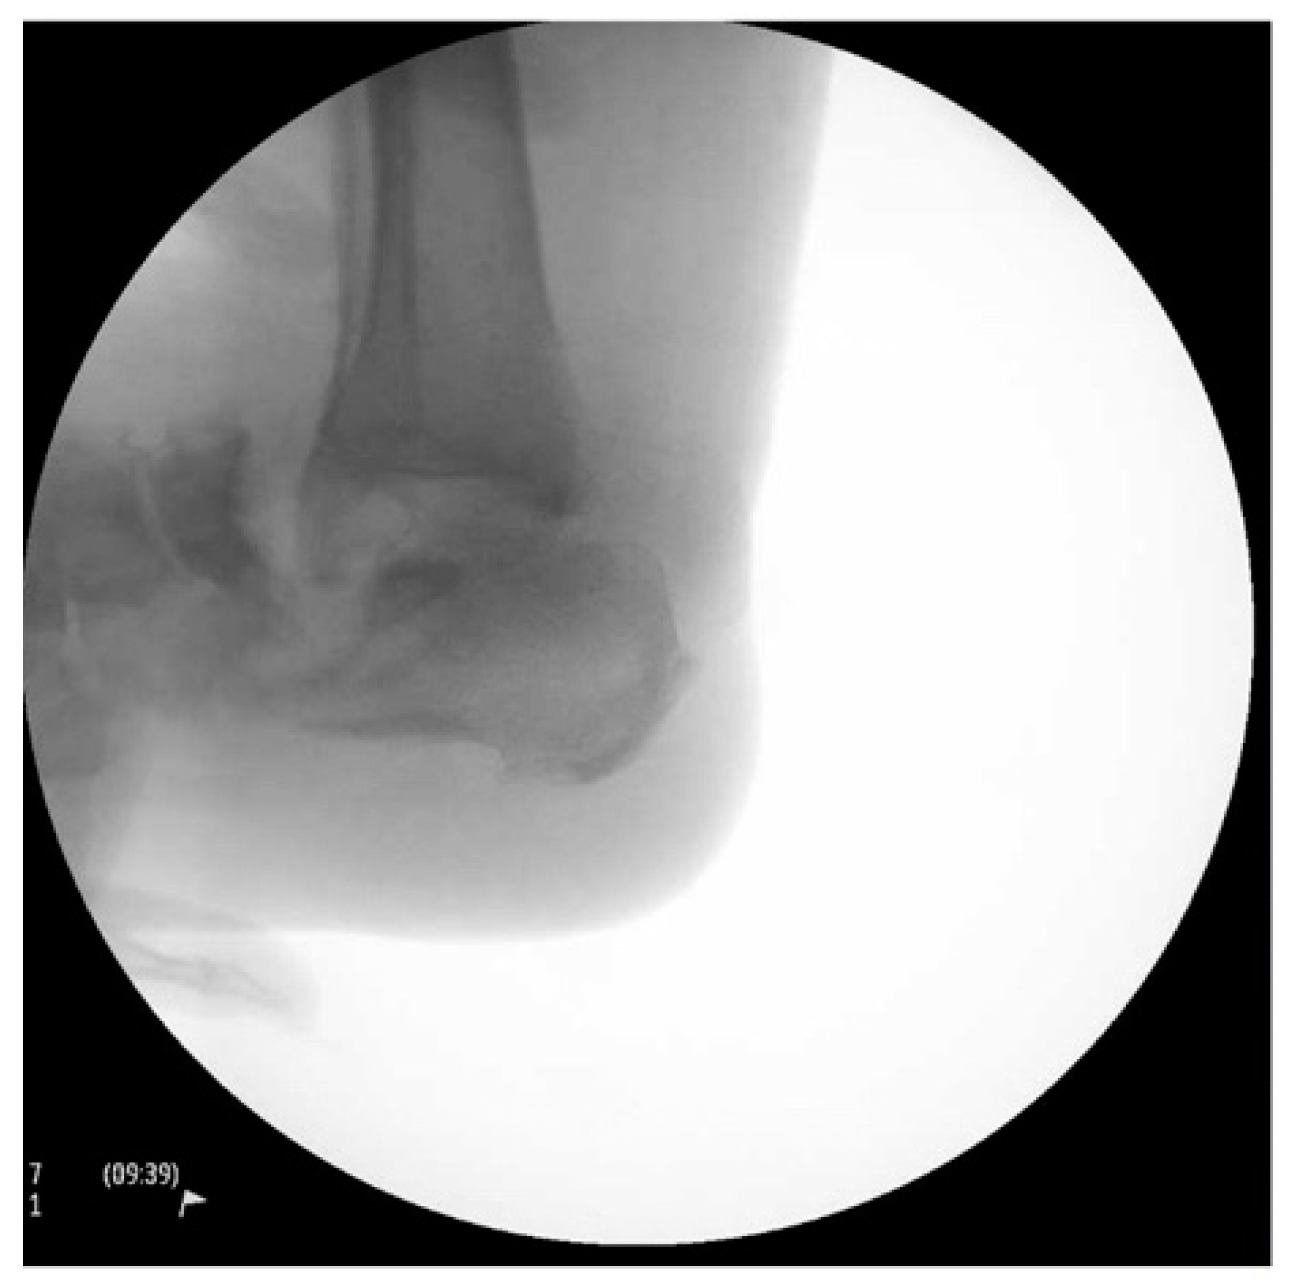

The sutures were removed at three weeks, confirming primary healing of all surgical incisions. The patient transitioned into a fiberglass cast, allowing protected weight bearing six weeks after surgery. At three months, a walking boot was provided for further protection, which she discontinued due to poor fitting. She was then advised to use diabetic shoe wear with a heel lift to address the 1.5 cm shortening of the operative extremity. The patient gradually returned to previous activities, fully weightbearing on the operative extremity. At the final one-year postoperative follow-up, patient had no pain or ulcerations in the foot (Figure 9). The final weightbearing radiographs demonstrated adequate osseous fusion with the stable position of the hardware (Figure 10). She was walking in her regular diabetic shoes with stable gait and plantigrade foot.

Figure 10. The final one-year postoperative weightbearing radiographs.